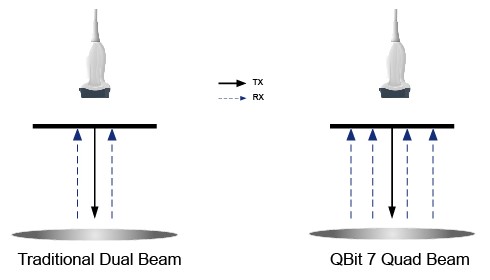

Q-beam - quad-beam - новая технология получения сигнала. Повышает разрешение и точность изображения, увеличивает частоту кадров, что особенно важно при изучении движущихся органов, например, сердца.